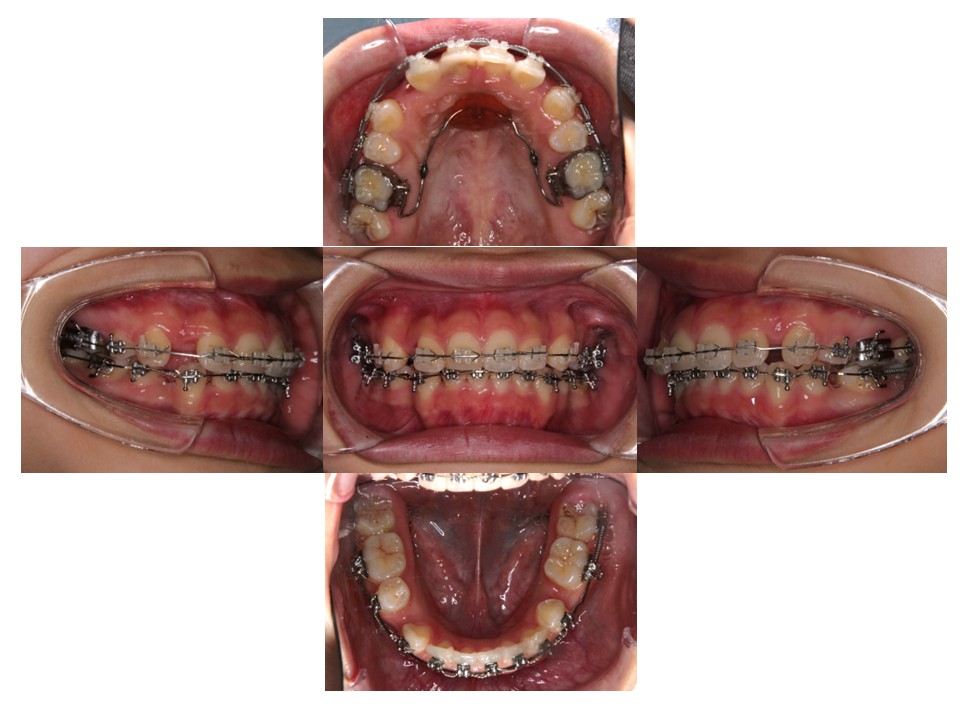

治療経過

上あごと下あごの歯を並べています。

上顎の前歯を後方移動しています